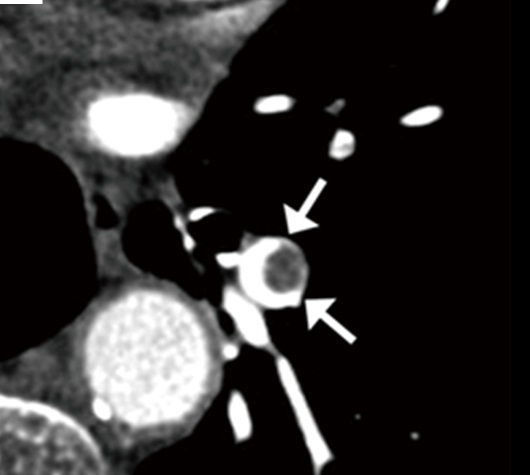

Inspired by the differnce we can make in the lives of people and the economic impact. AIMED helps detect pulmonary embolism early

We can extract just the vessel and embolus and the radiologist can only focus on those two.